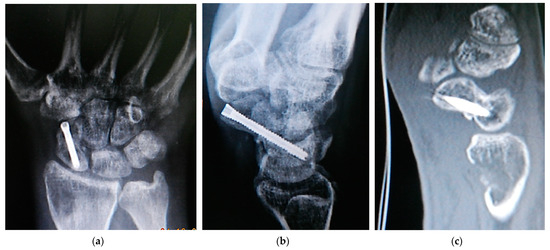

Strict immobilization with a short-arm cast including the first metacarpopharyngeal joint was performed for 10–12 weeks. In cases where K wires were used for fixation, they were removed at the time of cast removal. Then, physical therapy for active range of motion and muscle strengthening was initiated, and the patients were allowed to use their wrists for daily activities, while heavy loading was still postponed until the sixth month after surgery, based on the surgeon’s clinical and radiologic assessment. Immediate postoperative radiographs were used to assess the overall surgical procedure, whereas radiologic evaluations of union and graft incorporation were performed at 1.5, 3, and 6 months postoperatively. The presence of bony trabeculae joining the graft with both scaphoid fragments across the pre-existing nonunion site (Figure 4) and the absence of anatomic snuffbox tenderness were used to confirm the achievement of scaphoid union. Postoperative CT scans and contrast-enhanced MR imaging were reserved for suspected nonunion after the 6th month of surgery.

Figure 4. Postoperative radiologic investigation of scaphoid nonunion with resultant union achievement: (a) posteroanterior and (b) lateral x-rays showing scaphoid union and bone defect in the donor site of the distal Radius; (c) sagittal CT scan view showing incorporation of the pronator quadratus graft and the donor site bone defect.